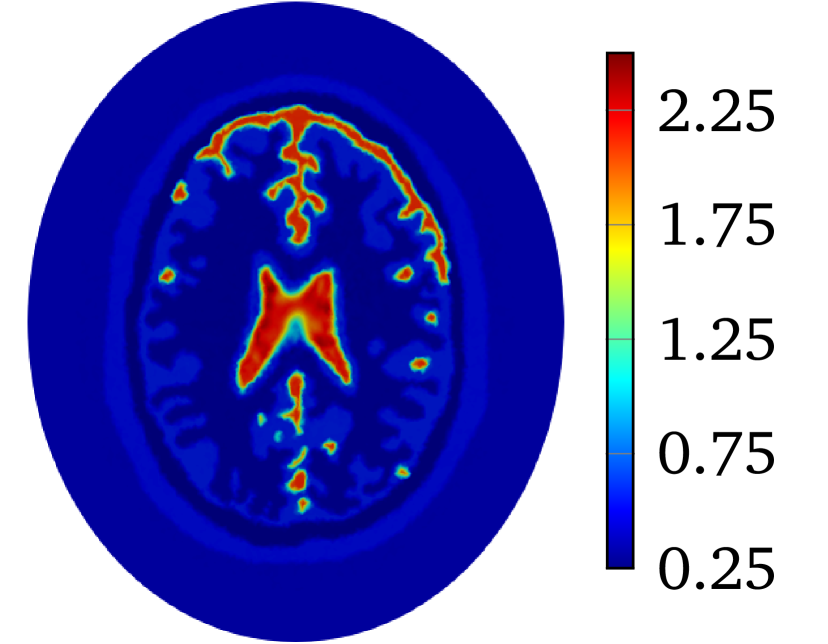

The second example is the human brain model shown in Figure 1(b). The considered tissues in this model include scalp (green, ), skull (blue, ), cerebro-spinal fluid (red, ), gray matter (yellow, ) and white matter (cyan, ). Refer to [5] for conductivities of different tissues. The shape of this model is close to an ellipse whose semi-major and semi-minor axes are and . The model is placed in an ellipse region with a background material (white, ). The semi-minor and semi-major axes of the region are and , respectively. The conductivity maps for the phantoms are piece-wise constant functions which will be mollified with

to produce with for 2D problem. The constant is selected so that . The value of is and for heart-lung model and human-brain model, respectively. The true smoothed distributions of for the two models are shown in Figure 2.